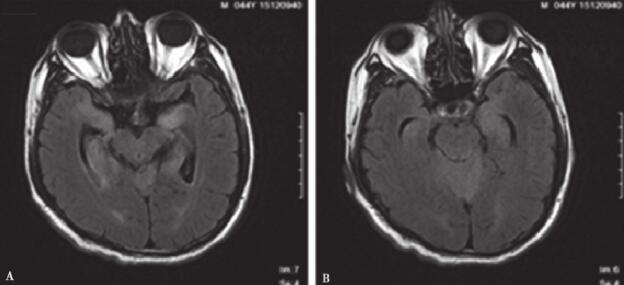

复查胸椎MRI:胸髓内可见异常信号,脊膜强化(图3)。脑脊液黏稠,不易流出。脑脊液蛋白45000mg/L。患者临床症状无改善,反应迟钝加重。讨论同意行颅内病变导航下穿刺活检。

图3 胸髓异常信号,脊膜强化

A.胸髓MRI T1像;B.胸髓MRI T2像;C.胸髓MRI增强像。胸髓内可疑异常信号,广泛脊膜强化